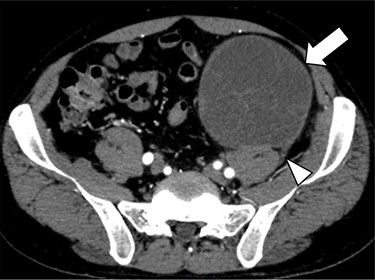

A 47-year-old man was admitted to his local hospital complaining of left abdominal pain. CT showed a 10-cm tumor in the left abdomen, and he was referred to our hospital. Contrast-enhanced CT confirmed a 10-cm hypodense solid mass in the retroperitoneum of the lower left abdomen. It showed that the tumor was contiguous with the third lumbar nerve, suggesting that it was a schwannoma (Fig. 1). Because the tumor was huge and its presence seemed to be associated with abdominal symptoms, we planned to resect it via less-invasive laparoscopic surgery.

Contrast-enhanced CT confirmed a 10-cm hypodense solid mass (arrow) in the retroperitoneum of the lower left abdomen. It showed that the tumor was contiguous with the third lumbar nerve (arrowhead), suggesting that it was a schwannoma.